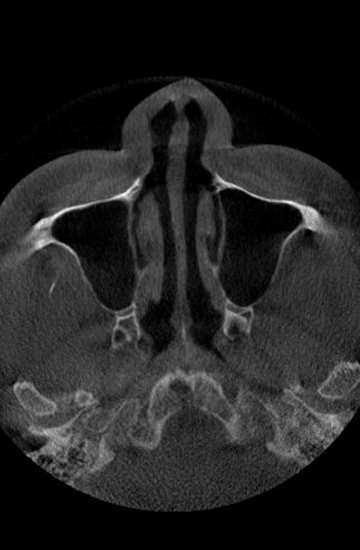

비중격만곡증이란?

비중격은 코를 둘로 나누는 벽으로,

휘거나 비틀리면 비중격만곡증이라 하며

C형·S형으로 구분되고 코막힘을 유발

• 비중격만곡증

정상 코

비중격만곡증 C형

비중격만곡증 S형